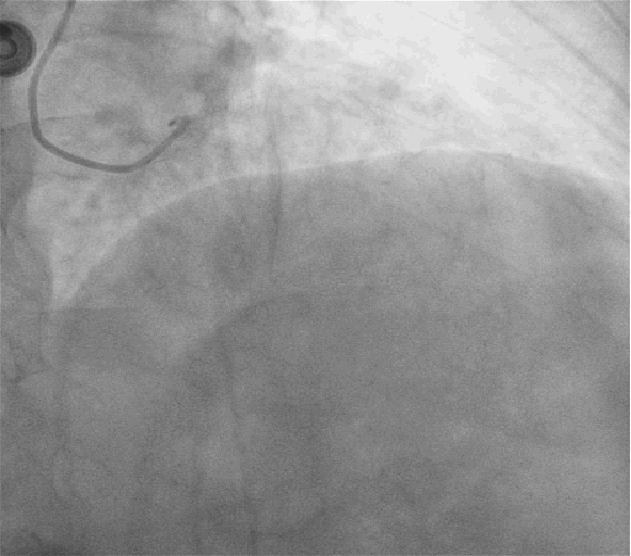

左图:AL1.0指引导管到位后,Sion导丝顺利送至右冠脉远段,迪马克2.5*15mm球囊到位困难,采用双导丝技术,球囊顺利到位后给予预扩张(10atm)。

右图:病变部位预扩后残余狭窄小于30%,病变部位未见明显夹层及撕裂,给予药物球囊鼎科2.5*20mm病变部位释放(8atm,60S)。

反复多体位造影提示:病变部位残余狭窄小于30%,未见明显夹层及撕裂,TiMi血流III级;